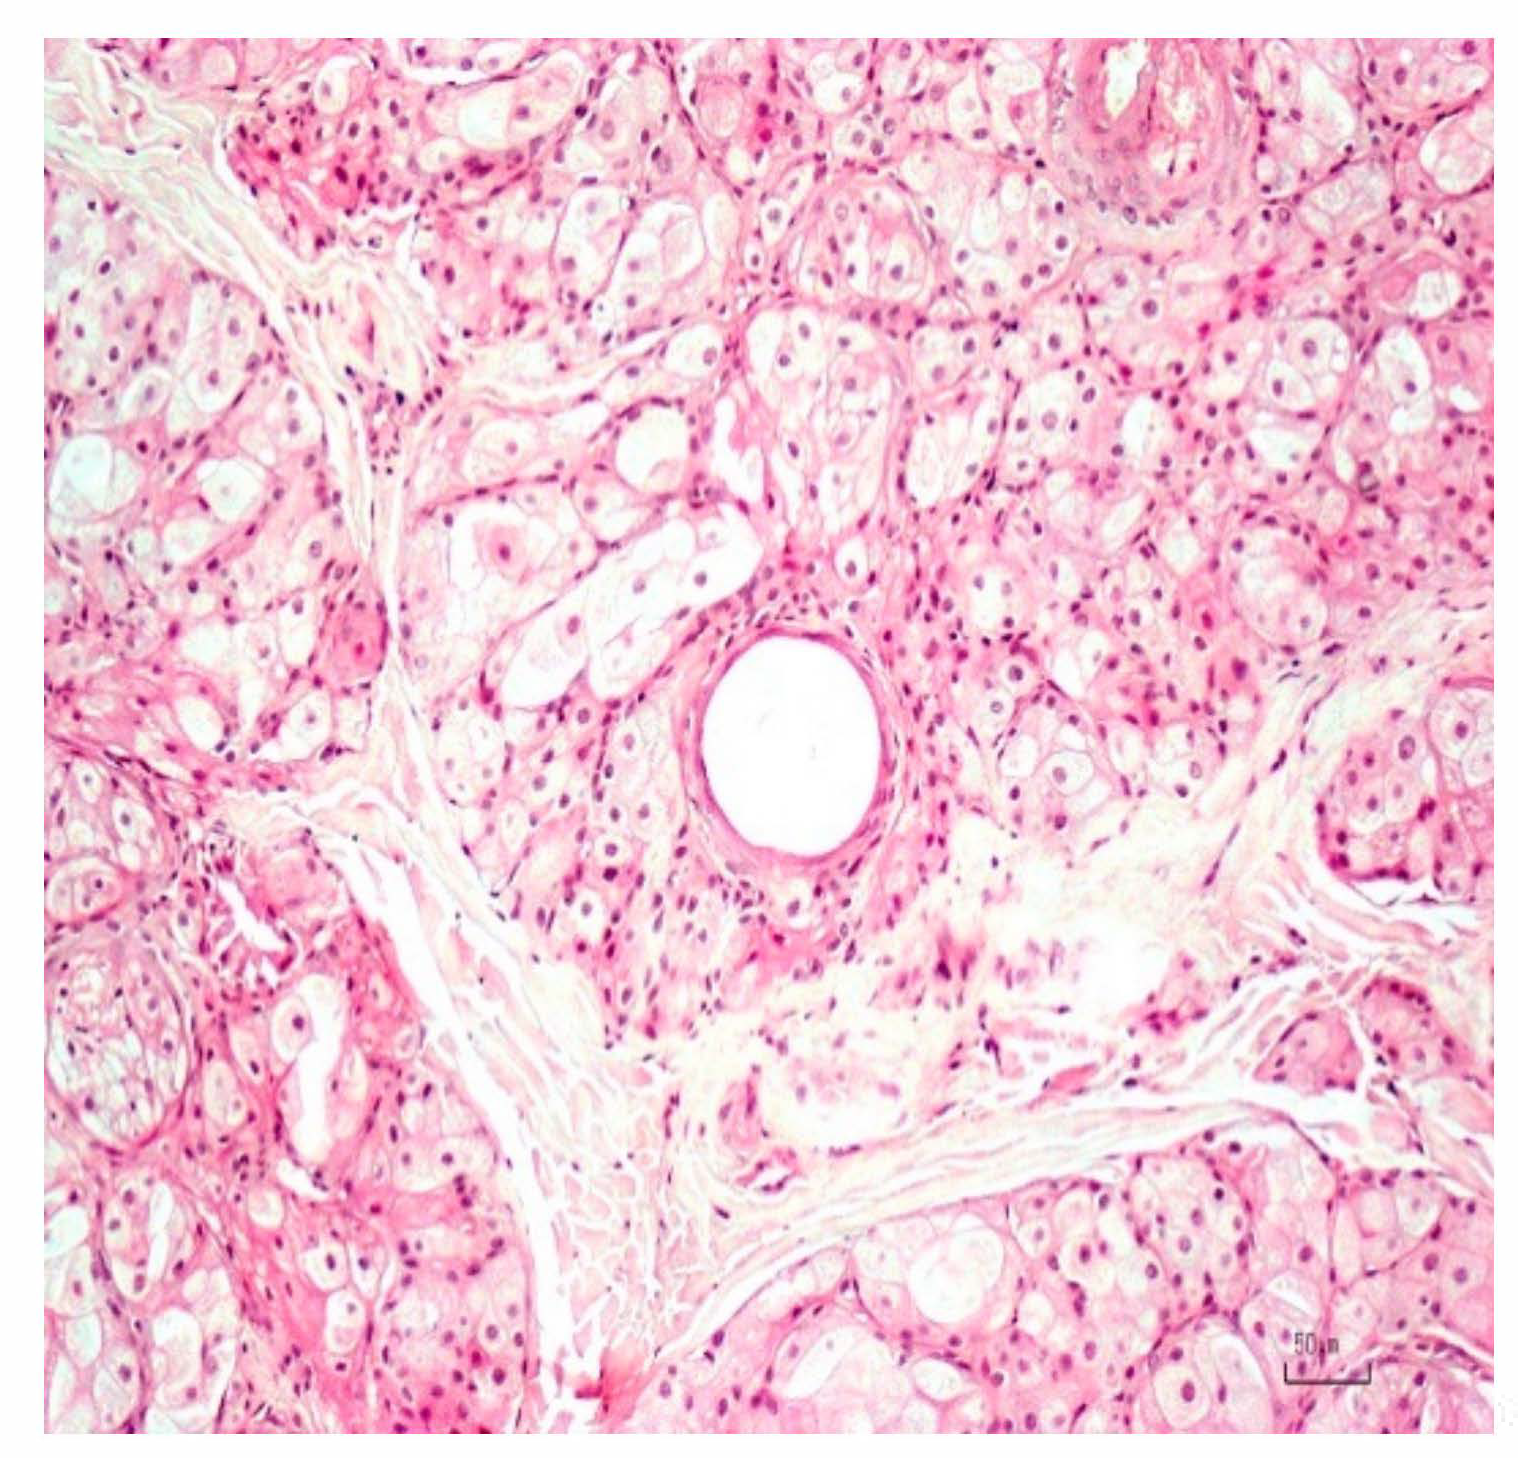

3. Results